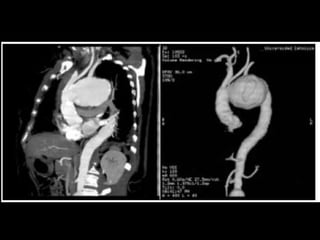

ANEURISMA